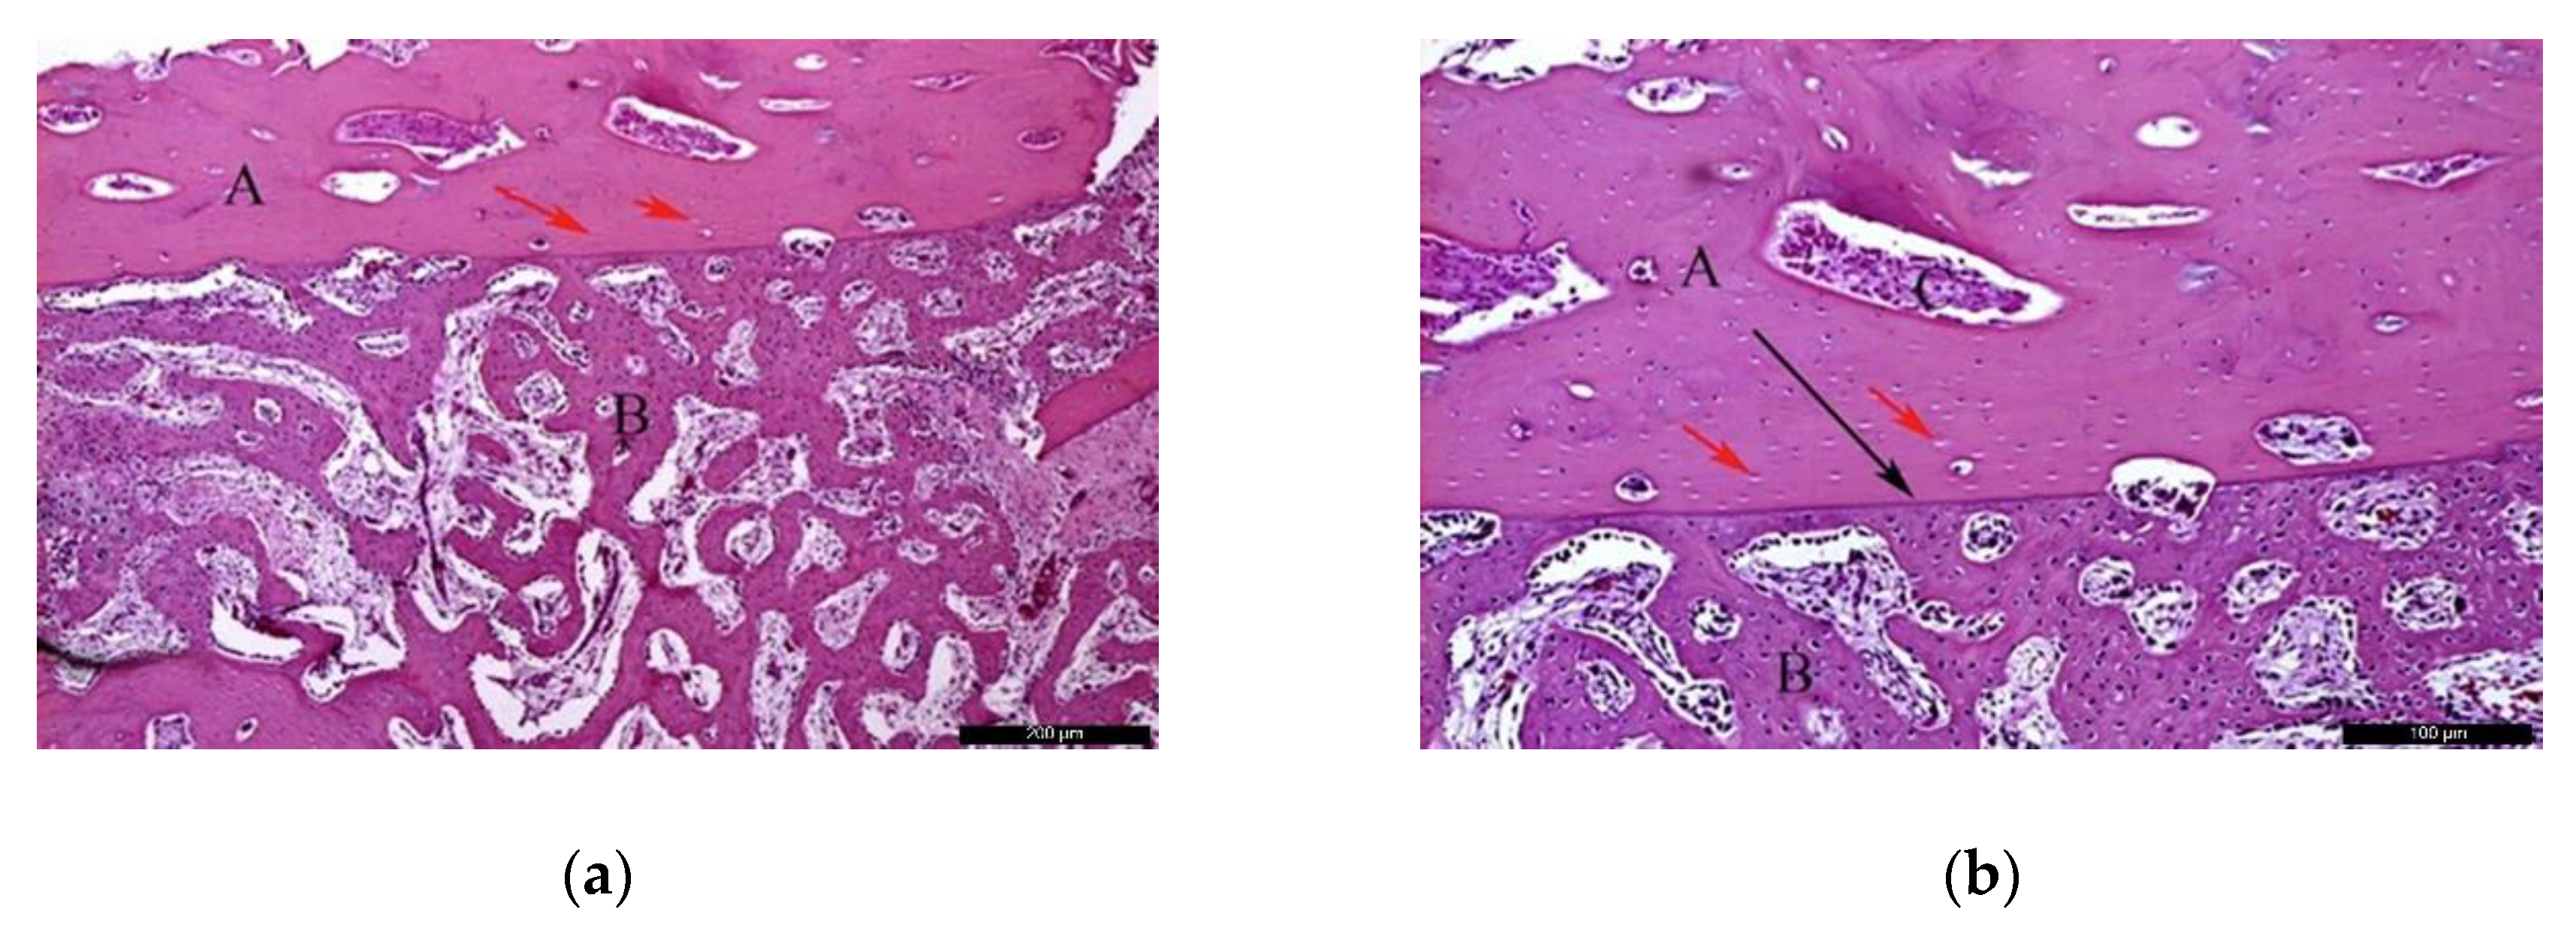

In the AG, after 30 healing days (Figure 3a), it was possible to observe the autogenous bone graft (A), and bone trabeculae under the receiving bed (B). The space between the graft and the recipient bed was occupied by bone tissue with a relevant number of trabeculae in the maturation stage with high cellular activity and good vascularization (C). Focusing on the graft (Figure 3b), autogenous bone (A) and newly formed bone (B) could be identified. In the inner part of the autogenous bone graft, small areas of resorption (black arrows) might indicate a phase of remodeling.

Figure 3.

Histological analysis of the autogenous group (AG) at 30 days. (a) Autogenous bone graft (A) positioned over the recipient bed (B), trabeculae in maturation stage and good vascularization (C); space previously occupied by the osteosynthesis screw is recognizable in (D). Hematoxylin and eosin stain at a magnification 40×; (b) Autogenous bone (A) newly formed bone (B), and small areas of resorption (black arrows). Hematoxylin and eosin stain at a magnification 125×.

In the AG, after 60 post-operative days (Figure 4a), it was possible to observe the autogenous bone graft (A) in contact with the newly formed bone (B). Internally, the presence of connective tissue areas might suggest a remodeling phase of the bone. The identification of anucleated cells could suggest the presence of osteoblasts (red arrows). At the microscopic examination (Figure 4b), it was possible to distinguish the autogenous bone graft (A) and newly formed bone (B) separated by a cement line (black arrow). In the inner part of the autogenous bone graft, connective tissue areas were noticed, confirming the remodeling phase of the bone. Osteocytes were clearly visible (red arrows).

Figure 4.

Histological analysis of the AG at 60 days. (a) Autogenous bone graft (A) in contact with the newly formed bone (B), and anucleated cells suggesting the presence of osteoblasts (red arrows). Hematoxylin and eosin stain at a magnification 40×; (b) Autogenous bone graft (A) and newly formed bone (B) separated by a cement line (black arrow) and osteocytes (red arrows). Hematoxylin and eosin stain at a magnification 125×.